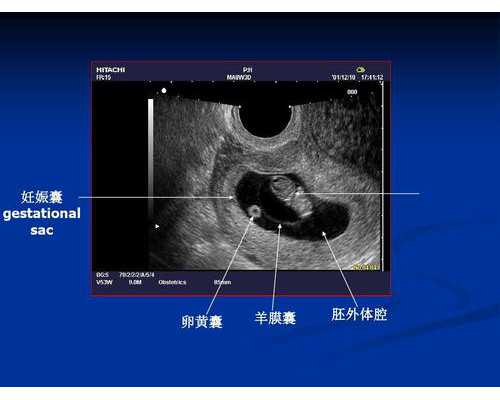

适用人群: 怀孕6周或以上孕妇